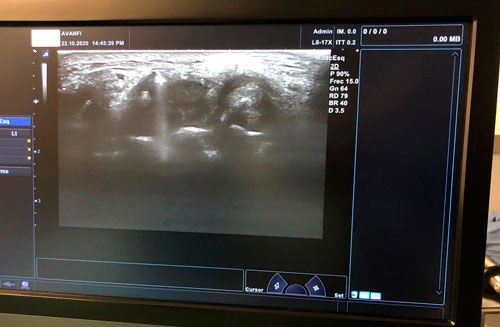

En pacientes candidatos a técnicas intervencionistas, la ecografía musculoesquelética puede añadir información anatómica de gran valor para localizar las bridas y planificar un abordaje ecoguiado más preciso.